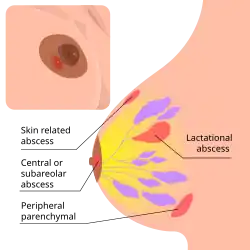

Subareolar abscess, also called Zuska's disease for non pregnancy related cases, is a subcutaneous abscess of the breast tissue beneath the nipple. It is a frequently aseptic inflammation and has been associated with squamous metaplasia of lactiferous ducts.

The term is usually understood to include breast abscesses located in the retroareolar region or the periareolar region[1][2] but not those located in the periphery of the breast.

Subareolar abscess can develop both during lactation or extrapuerperal, the abscess is often flaring up and down with repeated fistulation.